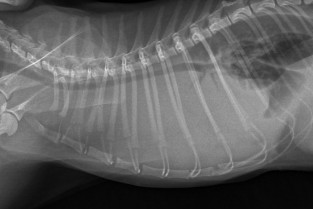

À travers l'étude de vidéos, une mise au point sur la sémiologie de la dyspnée et la marche à suivre face au patient dyspnéique.

• prendre en charge le patient en détresse respiratoire ;

• localiser une atteinte respiratoire en fonction du pattern de la dyspnée.

Les patients dyspnéiques : Tout comprendre en quelques secondes